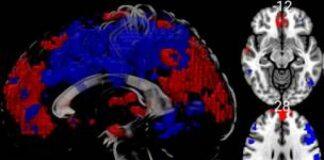

英国伯恩茅斯大学完成首例核磁共振_MRI脑部科研扫描

英国伯恩茅斯大学(Bournemouth University,简称:BU)首次使用其核磁共振_MRI扫描仪为首位参与科研的患者完成检测,作为探究冷水对于脑部活动的影响科研项目的数据参考之一。